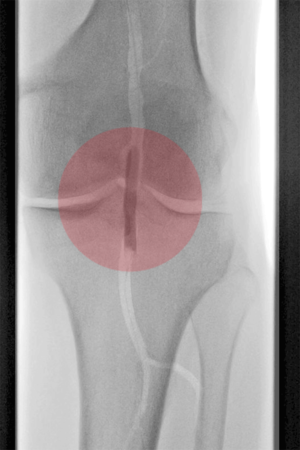

3. Stentimplantation – Einsetzen eines Stentes/ Gefäßstütze

Nach der Gefäßweitung kann durch Einrisse in den inneren Ablagerungen oder durch die Elastizität der Gefäßwand die Weitung nur ungenügend erfolgreich sein. Zur Stabilisierung des Befundes wird dann in diese Gefäßregion ein Stent eingesetzt. Dieser besteht aus einem feinen starren oder flexiblen Edelmetallgeflecht und kann auch mit Medikamenten gegen die Arteriosklerose oder zur Verhinderung der Bildung von Blutgerinnseln beschichtet sein.

Unter bestimmten Bedingungen, v.a. bei Verletzungen der Gefäße mit daraus resultierender Blutung oder lokalen Gefäßerweiterungen, werden Stents mit einer Ummantelung eingesetzt, die die Gefäßwand abdichten oder die Erweiterung überbrücken.